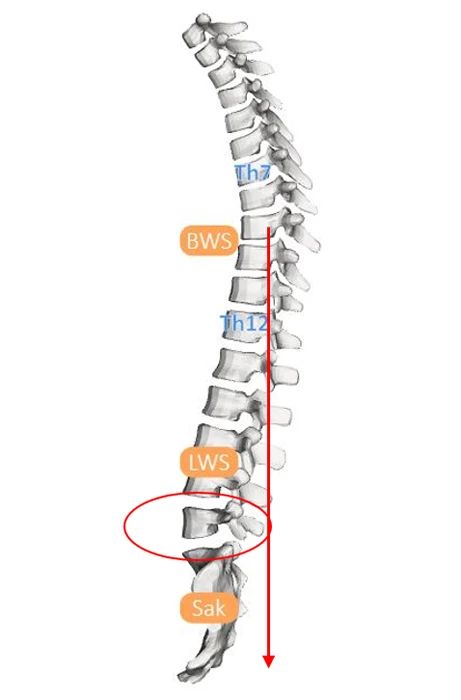

Bei der Körperhaltungsanalyse kann man sehen, wie die Körpersegmente gegeneinander verschoben sind.

Von unten nach oben:

• ist der Unterschenkel nach hinten gekippt

• der Oberschenkel nach vorne

• das Becken nach vorne verschoben

• der Brustkorb gebeugt und nach hinten verschoben

• der Schultergürtel und der Kopf nach vorne geschoben

Dieser Haltungstyp entspricht diesem Schema. Man kann sich vorstellen, dass eine solche geknickte Säule an den Knickungsstellen durch das Gewicht der Körpersegmente überlastet werden kann.

Schema Haltungstyp